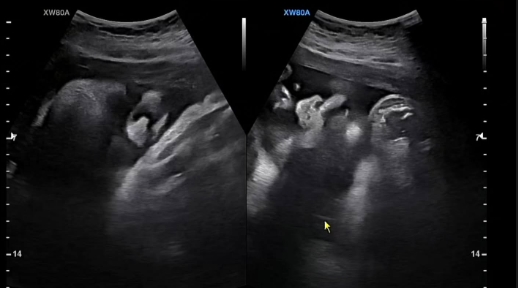

그런가 하면 정주리는 "아직 23일이나 남았는데 3.4키로??!"라며 출산을 23일 앞둔 초음파 사진을 공개, 출산이 임박한 근황을 전하기도 했다.